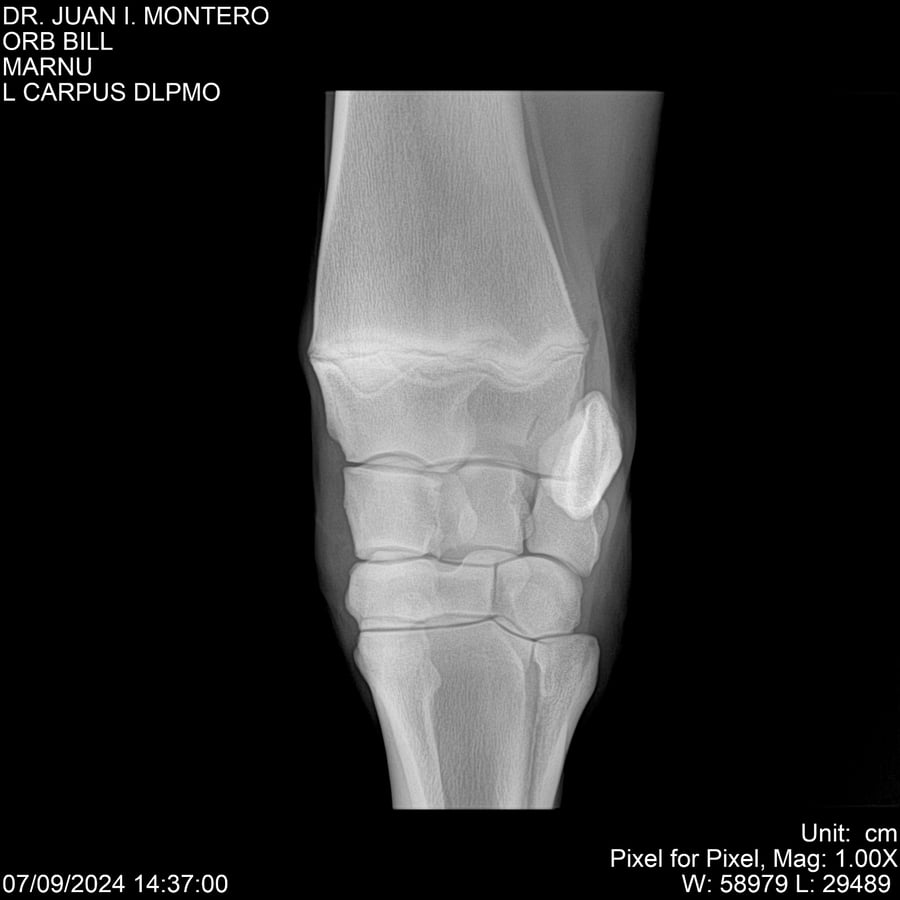

LOTE 7, ORB BILL 🔥 🔥 🔥 Lote Anterior Volver al remate Lote Siguiente Ficha Contacto Montevideo - Ficha del Lote Identificador: #282523 Categoría: Yeguarizos Montevideo - 83 Visualizaciones ClicData Contacto Empresa: Abelenda N. R., Walter Hugo Nombre*: Teléfono* : E-mail* : Mensaje Enviar Registrese gratis Este contenido Exclusivo está disponible sólo para usuarios registrados Ingresar